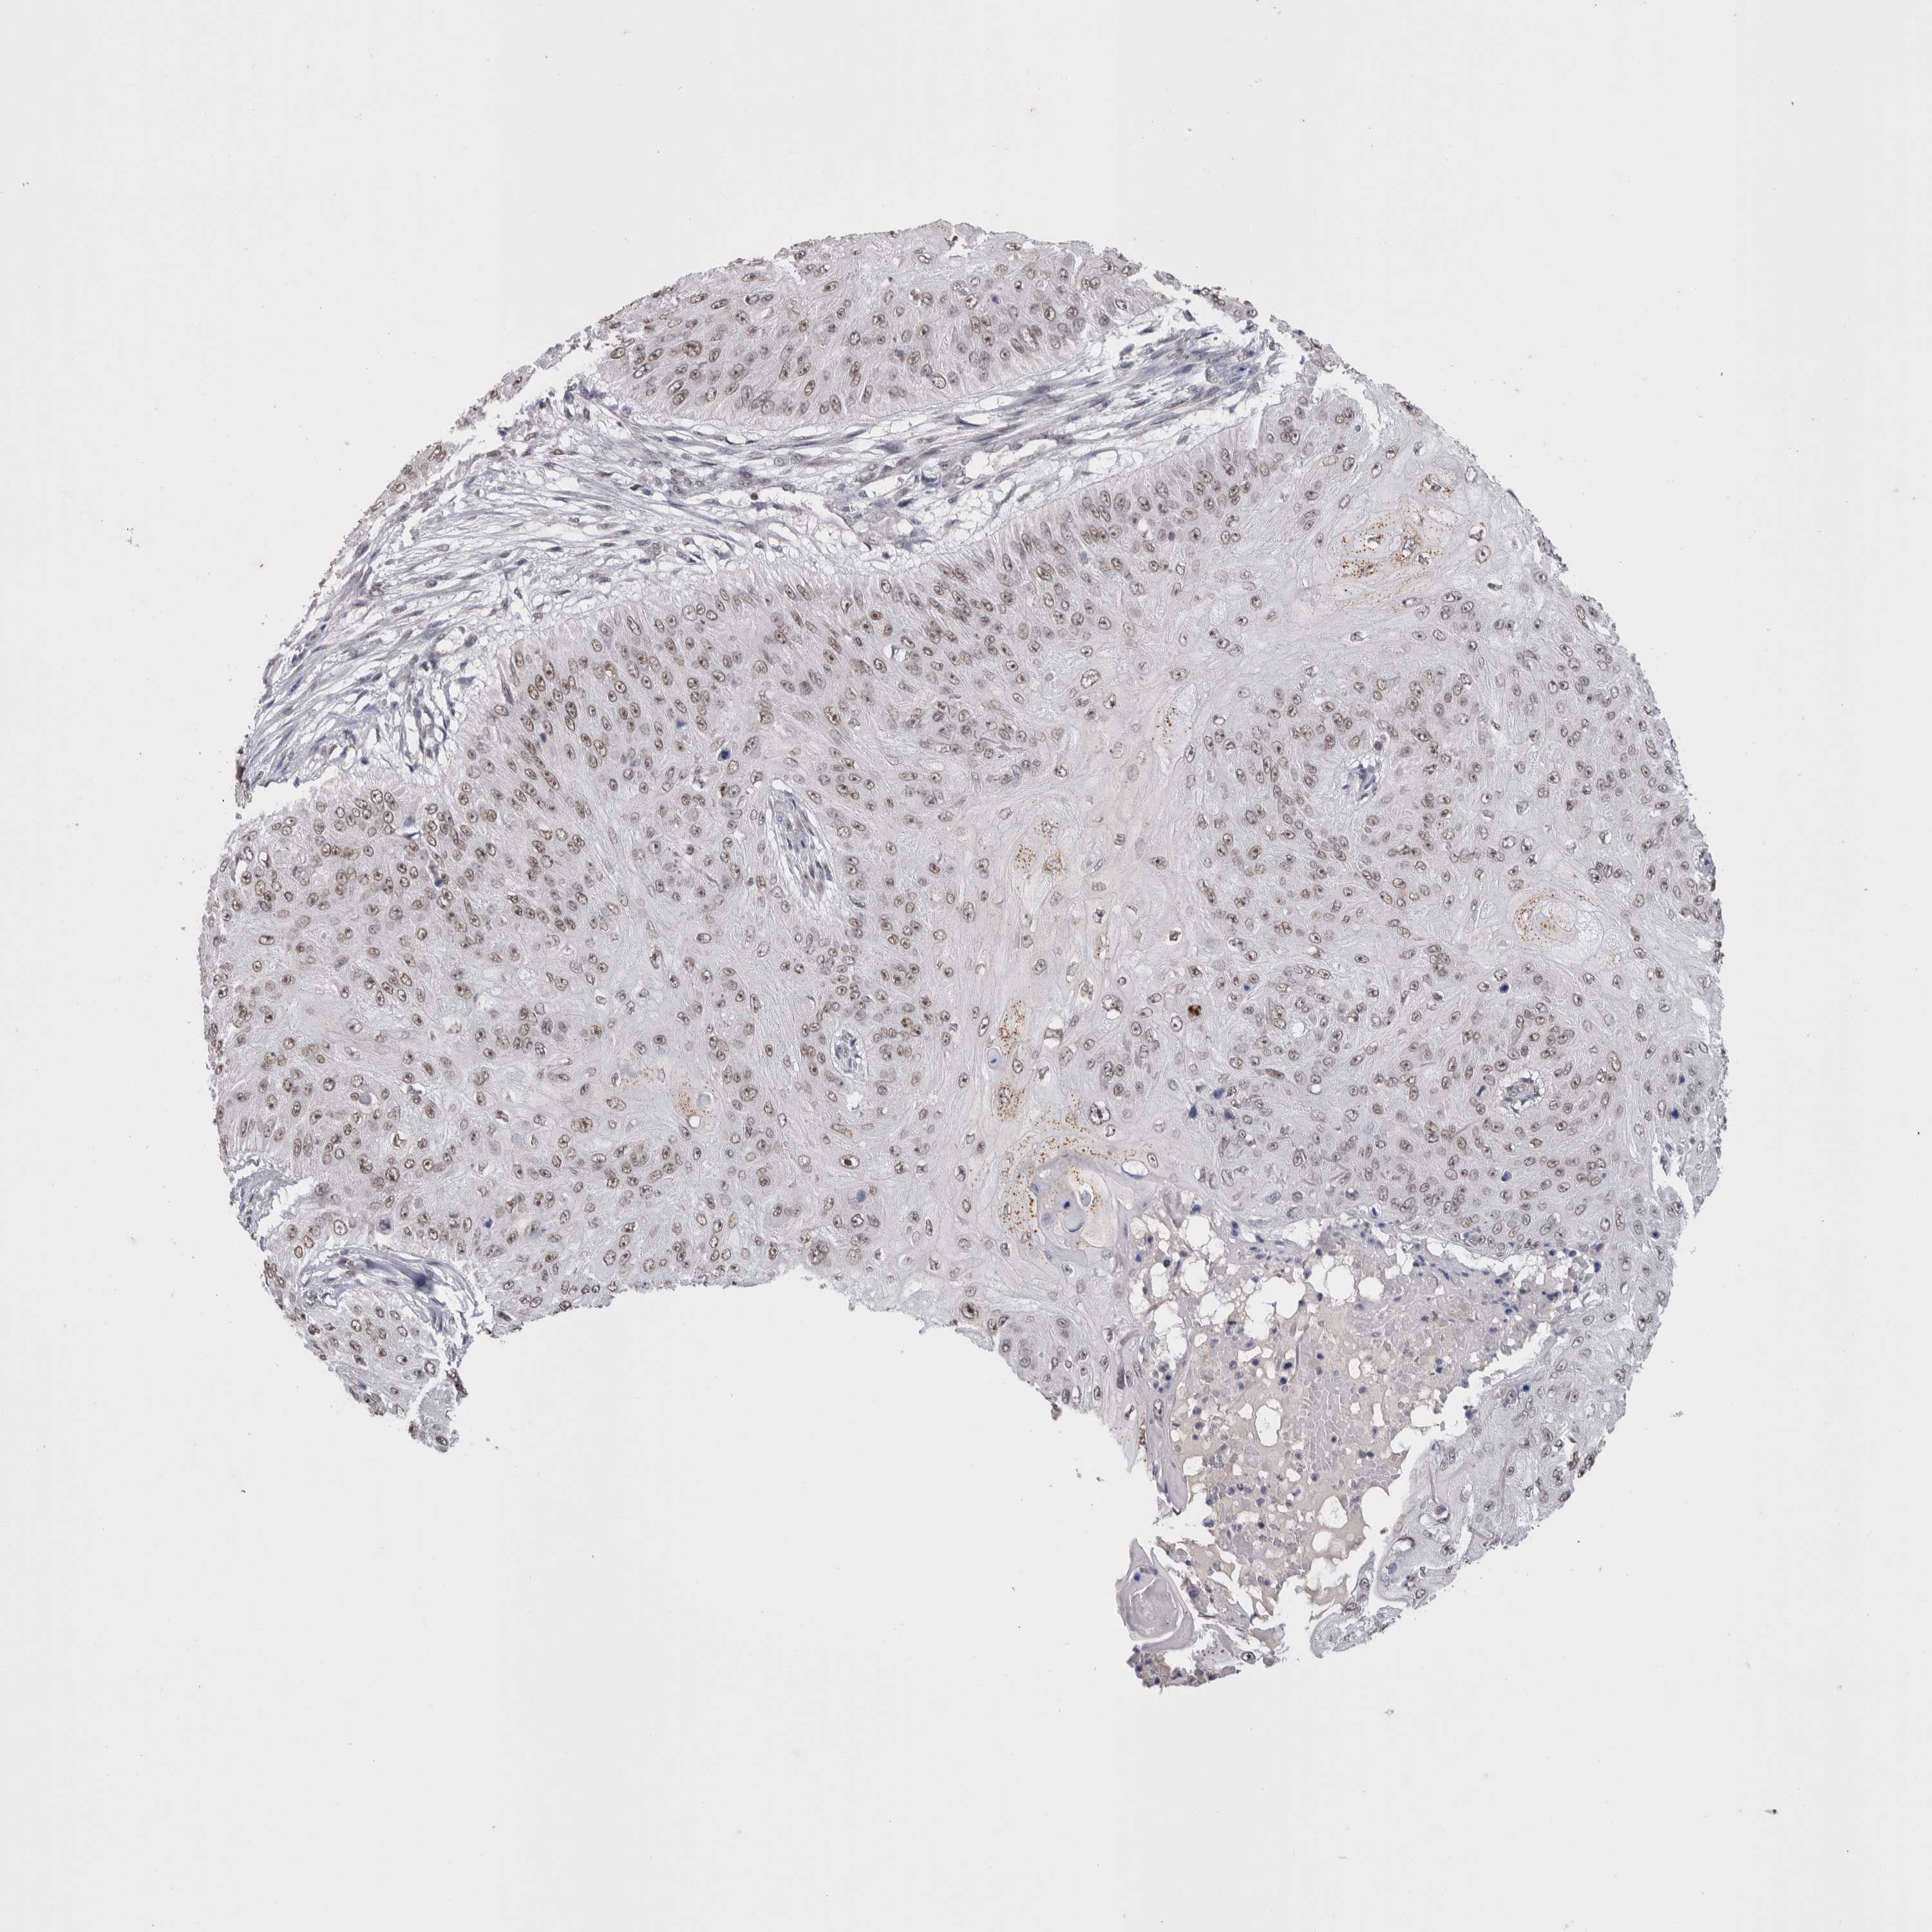

SKIN CANCER - Protein expressioni

A mouse-over function shows sample information and annotation data. Click on an image to view it in a full screen mode. Samples can be filtered based on level of antibody staining by selecting one or several of the following categories: high, medium, low and not detected. The assay and annotation is described here.

Antibody stainingi

Antibody staining in the annotated cell types in the current human tissue is reported as not detected, low, medium, or high, based on conventional immunohistochemistry profiling in selected tissues. This score is based on the combination of the staining intensity and fraction of stained cells.

Each image is clickable and will lead to virtual microscopy that enables deeper exploration of all samples and also displays staining intensity scores, fraction scores and subcellular localization as well as patient and tissue information for each sample.

Antibody CAB002224

Staining

High

Medium

Low

Not detected

Intensity

Strong

Moderate

Weak

Negative

Quantity

>75%

75%-25%

<25%

None

Location

Nuclear

Cytoplasmic/membranous

Cytoplasmic/membranous,nuclear

Basal cell carcinoma

Adnexal tumor, benign